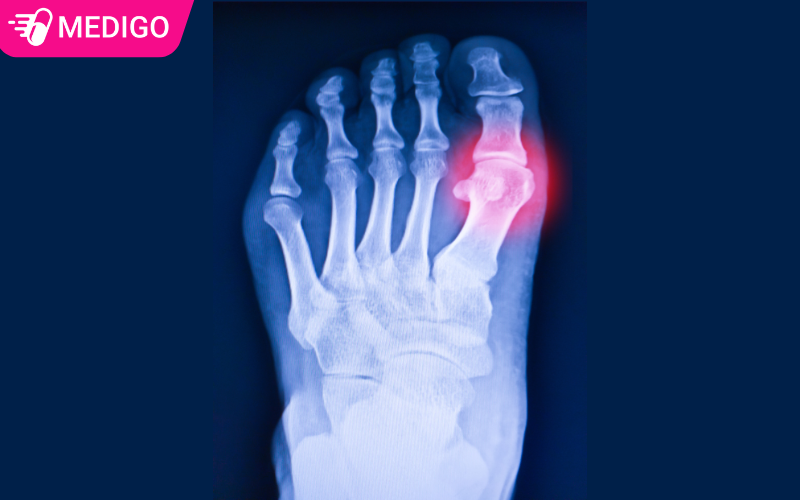

2.3. Vị trí đau đặc trưng: Ngón chân cái

Hơn 50% các ca Gout lần đầu đều xuất hiện ở khớp ngón chân cái. Tuy nhiên, Gout cũng có thể tấn công các khớp khác như:

- Khớp cổ chân, gót chân.

- Khớp đầu gối.

- Khớp ngón tay, cổ tay, khuỷu tay.